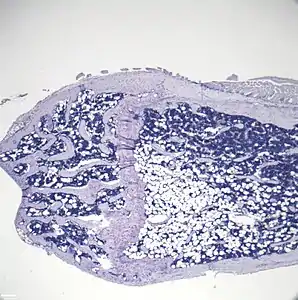

- Histologic sections demonstrating Marrow Adipocytes

Representative distal femur histologic section of a 16-week-old C57BL/6 mouse after 6 weeks of calorie restriction demonstrating an increased quantity of marrow adipocytes.